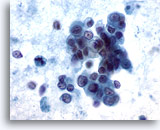

画像 3

肝FNA – 良性肝細胞

核はわずかに大小不同であり、反応性変化を来した肝細胞に典型的な低N/C比を示します。微小な細胞質空胞および細胞質内色素がみられます。

60倍

画像 3

肝FNA – 良性肝細胞

核はわずかに大小不同であり、反応性変化を来した肝細胞に典型的な低N/C比を示します。微小な細胞質空胞および細胞質内色素がみられます。

60倍